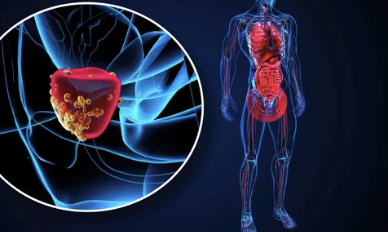

1. 전립선암이란 무엇인가

전립선암은 남성에게만 있는 장기인 전립선(prostate)에 생기는 암입니다.

전립선은 방광 아래, 요도를 감싸며 정액 일부를 만드는 역할을 하죠.

하지만 세포가 비정상적으로 증식하면 전립선암으로 발전합니다.